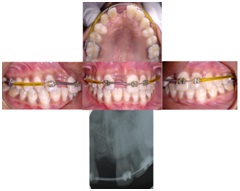

An arch wire supporting with the sleeve between 16 and 13 on the right side and on the left side between 26 and 22 was placed (Classic orthodontics, USA). NiTi Open coil spring (. 010 inches, 3M, USA) was incorporated between 12 and 21 for space regaining [Table/Fig-4], then the arch wire was stabilized with ligature ties (3M Unitek, USA).

The patient was recalled after two-months for follow-up and it was observed that the desirable space was regained, as depicted in the intraoral photographs and IOPA [Table/Fig-5].